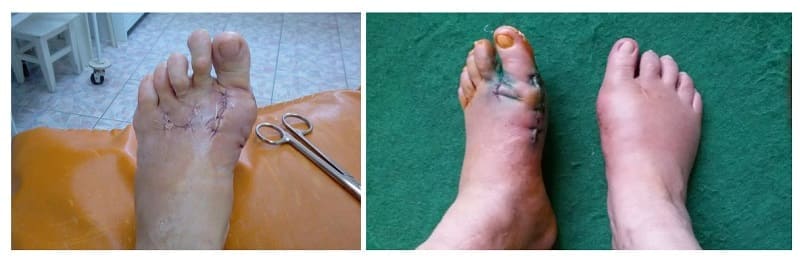

Профессор Чжу показал слайды с результатами операций по удалению “косточки на ноге” и призвал прекратить издеваться над людьми. Он утверждает, что это чаще всего приводит к инвалидности.

В 87% случаев косточка вырастает снова! Кроме того, после операции остаются уродливые шрамы, которые будут с человеком на протяжении всей его жизни.

Профессор Чжу: “Такого ли результата ждут пациенты? Если после одной операции надо делать другую - пластическую, и еще не факт, что все пройдет успешно!

Посмотрите на результат запущенности и халатного отношения людей к своему здоровью. Через несколько лет эти люди будут инвалидами и не смогут себе помочь. А есть и те, кто уже не может жить полноценной жизнью.